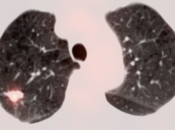

• The utility of PET/CT lies in its assessment of regional nodes and distant metastatic disease.

• Distant Disease: Most commonly to the liver, peritoneum, lung and bone.